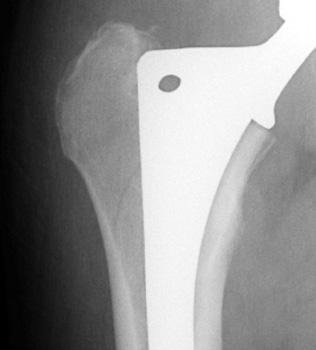

Intraoperative fracture of the proximal femur.